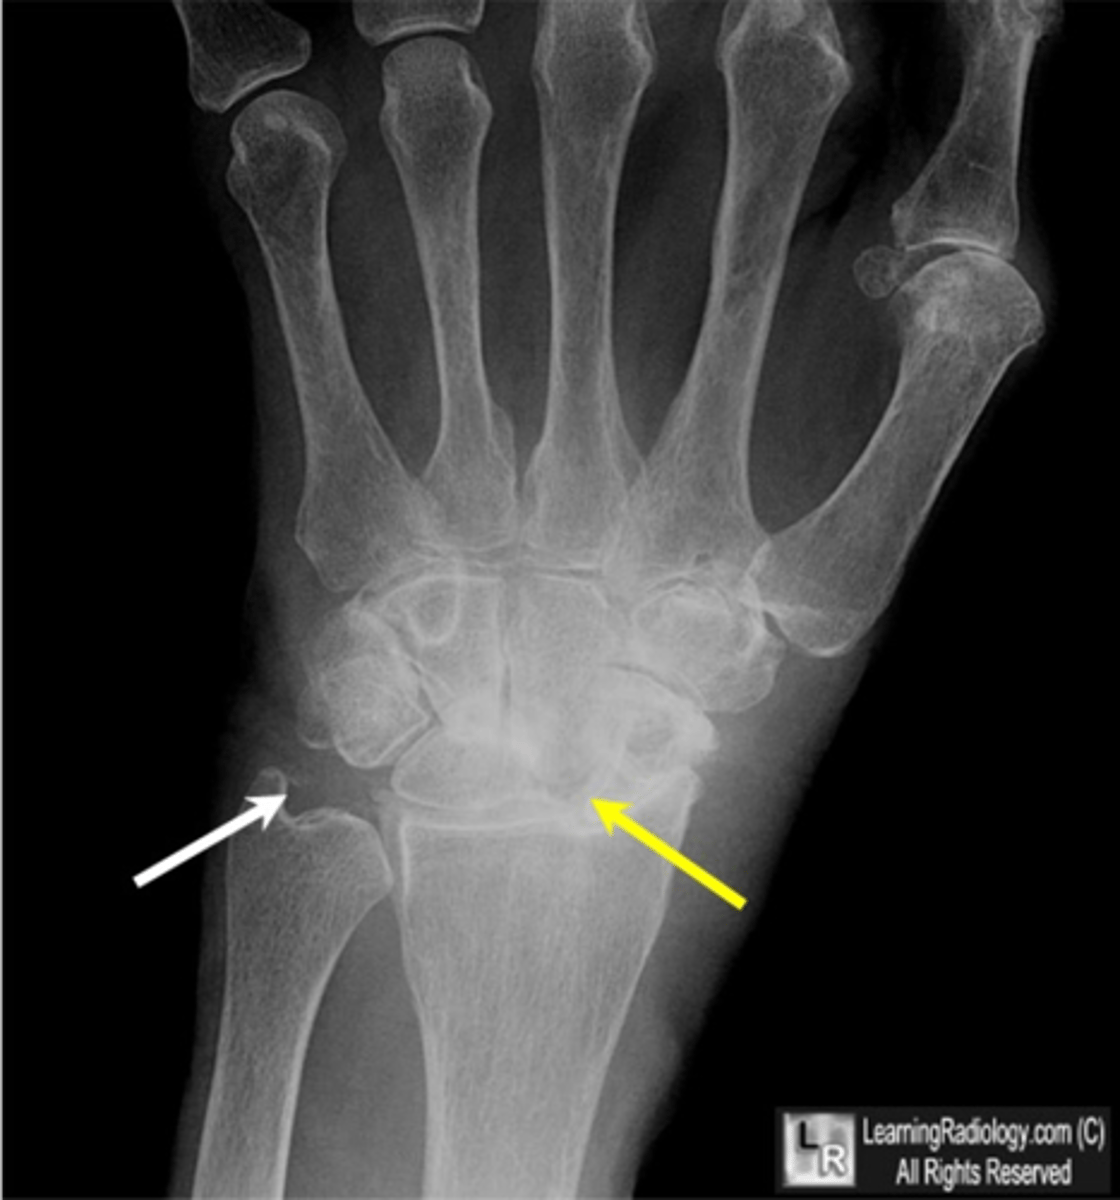

- Dense soft tissue tophi (swelling)

- Bone erosions

- Overhanging margin sign

- Secondary degeneration

- 1st MTP MC joint

State the radiographic findings of gout

- SLAC wrist (scapholunate advanced collapse)

State the radiographic findings of calcium pyrophosphate dihydrate crystal deposition disease (CCPD)